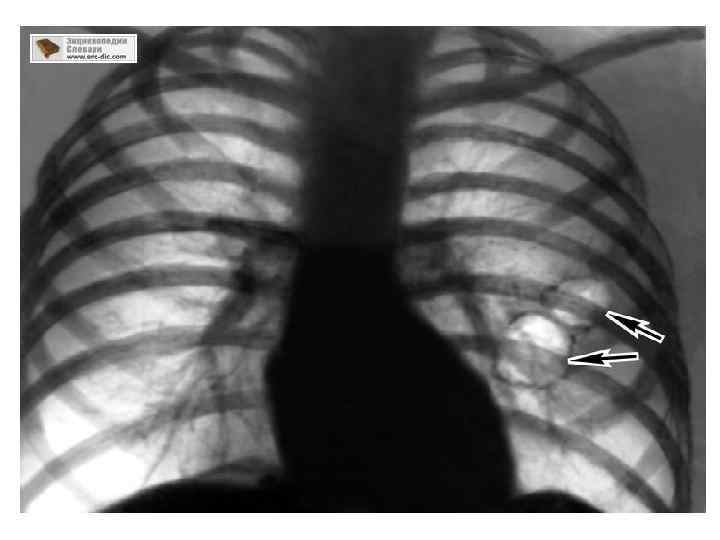

Өкпе эмфиземасының патологиялық анатомиясы Ауа кернеп, ұлғайған, бозғылт түсті, жұмсақ, қабыспайтын өкпенің алдыңғы жақ жиектері көкірек қуысын жауып т±рады. Кескенде ткані сықырлайды. Іргесі қалындаған бронхылардың саңылауынан қысќанда шырышты ірің шығады. Бронхылардың кілегейлі қабықшасына клеткалар шоғырланып, бокалша клеткалар көбейеді; олардың єр жері, єсіресе ұсақ бронхылардың бұлшықетті қабаты қалыњдайды. Бронхиолалар басымырақ өзгерсе, ацинустың проксималдық бөлімдері (1 -ші және 2 -ші ретті тарамѓа жататын респирациялық бронхиолалар) кеңейеді, ондай эмфизема центрацинустық деп аталады. Процесс ірірек бронхыларда басымырақ болса, ацинус түгел кеңейеді, бұл — панацинустыќ эмфизема.

Эмфизема кезінде альвеолалар созылады, саңылауы кеңейді, біріңғай салалы бұлшықетті будалар гипертрофияланады, кейін дистрофияға ұшырайды. Эластикалық талшықтар азаяды, капилиярлар қуысы бос қалады. Микробейнесі: Өкпенің көлемі ұлғаяды, бозарады, кескенде сықыр естіледі. Идиопатиялық эмфизема кезінде бұл құбылыстың диффузды, ал салдарлық эмфизема кезінде ошақты орналасуын байқауға болады. Макробейнесі: